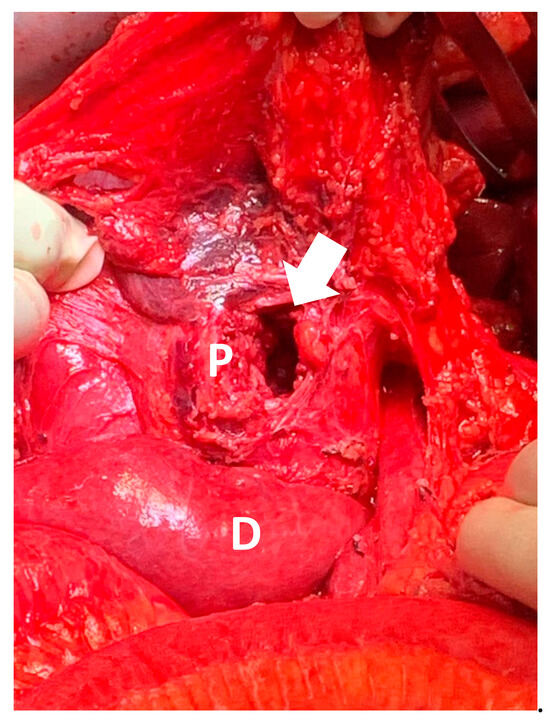

A 32-year-old man presented to an Australian level 1 trauma center following a gunshot wound to the abdomen from close range, with an entry wound left of midline and no exit wound. He was hemodynamically stable, with a subsequent multiphase computed tomography (CT) scan (Figure 1) demonstrating injury to the head of the pancreas with associated hematoma, perforation of the transverse colon, a right kidney laceration with hematoma, and the bullet within the right posterior pararenal space. The CT scan also suggested active bleeding from the inferior pancreaticoduodenal artery (IPDA), with likely injury to the common bile duct (CBD) and duodenum at the ampulla, representing an American Association for the Surgery of Trauma (AAST) grade V extrahepatic biliary tree injury. An emergency laparotomy was subsequently performed. At the time of anesthesia induction, the patient had a supported blood pressure of 130/60 mmHg and a heart rate of 110, with a base excess of −3.3. As part of a massive transfusion protocol, a total of 4 units of packed red cells were administered during pre-operative resuscitation.

During the procedure, a non-expanding retroperitoneal hematoma was identified, indicating a venous source of hemorrhage with retroperitoneal self-tamponade. Access to the hematoma revealed anterior and posterior defects in the infrarenal IVC (AAST grade III abdominal vascular injury). Hemostasis of the IVC was achieved by proximal balloon catheter occlusion, with venorrhaphy of the posterior and anterior IVC defects using 6-0 prolene (Figure 2). The total IVC occlusion time was approximately 6 min. A right nephrectomy was performed to control hemorrhage, along with an extended right hemicolectomy. The bullet was retrieved during the procedure and sent with the operative specimens for histopathology and subsequent forensic pathology. Intra-operatively, the decision was made to perform a pancreaticoduodenectomy due to a 4 cm defect in the head of the pancreas and associated duodenal perforation (Figure 3 and Figure 4), representing an AAST grade V pancreatic injury. During the procedure, the patient had an estimated blood loss of 800 mL, requiring a further unit of packed red cells and one unit of cryoprecipitate. Cell salvage was not used.

Figure 1. CT trauma findings. (A) Bullet (blue arrow) evident in retrorenal space with associated hematoma. Blush and hematoma evident from IPDA. Free air from duodenal perforation. Aorta intact. (B) Loss of IVC wall continuity (red arrow). (C) Portal vein spared, but CBD and duodenum perforated (green arrow). (D) Bullet evident in retrorenal space with associated hematoma.